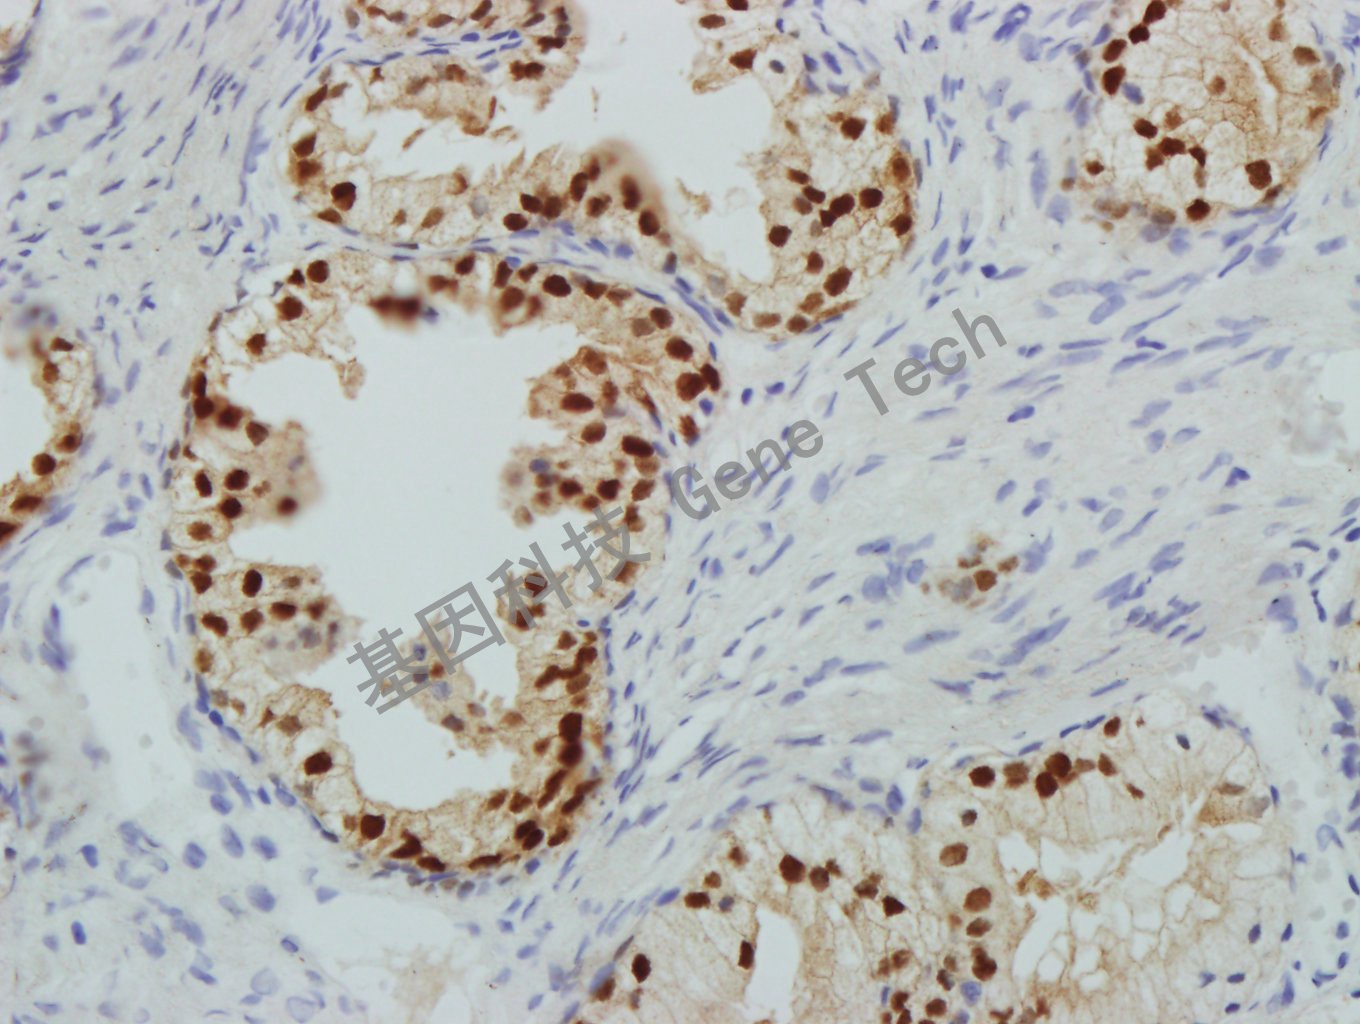

前列腺石蜡切片,用 NKX3.1(GT2260)染色,细胞核阳性,DAB 显色。(40×)